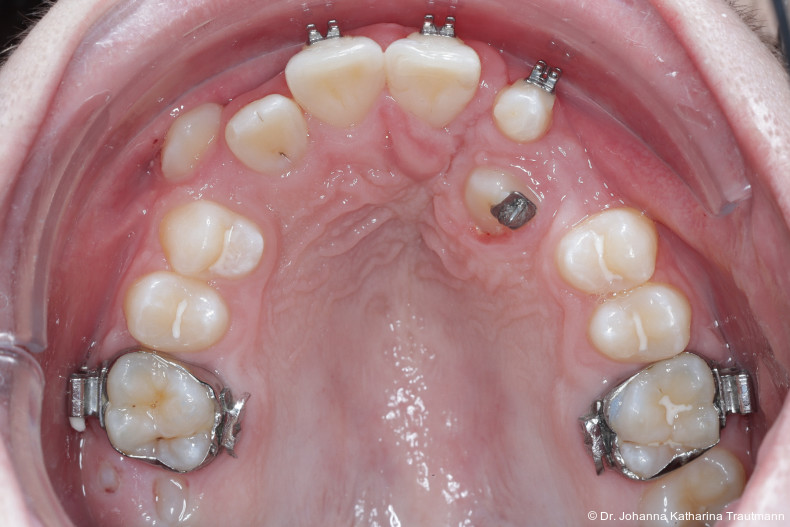

Das Fernröntgenseitenbild zeigte eine skelettale Klasse IIAnomalie mit einem Wits von 5,6 mm, bei einer tiefen Konfiguration (ML NL = 16,5°) mit bialveolär retrudierten Fronten (OK1NA = 5,9°; UK1NB = 10,4°), was sich auch in der Modellanalyse widerspiegelte. Hier zeigte sich zudem ein schmaler Oberkiefer mit multiplen Kippungen und Rotationen in der Front, einem hypoplastischem 22 sowie einer Mesialwanderung des 16. Des Weiteren zeigte sich eine asymmetrische Bisslage mit 1 PB distal rechts und ½ PB distal links bei einem Overjet von 2,5 mm sowie einem Overbite von 5 mm. Während im Unterkiefer bereits die zweite Zahnwechsel phase begonnen hatte, zeigte sich im Oberkiefer noch kein Wechsel in den Stützzonen. Gerade bei Patienten mit Spaltbildungen ist eine engmaschige Überwachung des Durchbruchs der oberen Eckzähne essenziell. Während bei der Allgemeinbevölkerung die Prävalenz von verlagerten Eckzähnen bei ca. 2,8 Prozent liegt2, ist diese bei Patienten mit Lippen-Kiefer-Gaumen-Spalten um den Faktor 10 erhöht.3, 4 Als klassische Risikofaktoren gelten zudem Platzmangel, transversale Enge aber auch Fehlstellungen, Nichtanlagen oder Hypoplasien der zweiten Schneidezähne. Diese übernehmen normalerweise die Funktion der Leitschiene für den S-förmigen Durchbruch der Eckzähne. Im vorliegenden Patientenfall kommen also mehrere Risikofaktoren für eine Verlagerung zusammen, was die rechtzeitige Diagnostik zur Abklärung einer Durchbruchsproblematik rechtfertigt. Da im Spaltbereich auch zusätzlich ein ausgeprägtes Knochendefizit vorliegen könnte, sollte auch immer die Option einer sekundären Osteoplastik abgewogen werden, deren Indikation und Timing optimal zum Durchbruch der Canini angepasst werden sollte.5

Zur genaueren Diagnostik der Lage beziehungen der Eckzähne und des Knochenangebotes im Spaltbereich kann neben den kieferorthopädi schen diagnostischen Unterlagen laut der S2 kLeitlinie Dentale digitale Volumentomografie6 auf eine dreidimensionale Bild gebung zurückgegriffen werden. In dieser zeigte sich eine vestibuläre Verlagerung des 13, eine palatinale Verlagerung des 23, sowie ein deutliches Knochendefizit im Spaltbereich mesial des hypoplastischen 22 (Abb. 2). Nach Auswertung der 3D-Daten erschien aufgrund der palatinalen Lage des 23 eine invasive Operation wie eine sekundäre Osteoplastik keinen entscheidenden Vorteil für die weitere Be handlung zu haben. In Rücksprache mit der Mund-Kiefer-Gesichtschirurgie der UMG wurde daher auf die OP verzichtet und initial die kieferorthopädische Therapie in den Vordergrund gestellt.

Nach transversaler Nachentwicklung der Maxilla mittels GNE nach Veltri wurde der Zahn 23 geschlossen freigelegt und an einem individualisier ten TPA nach distal angebunden. Zur Aufrichtung der Front und Mesialisierung des hypoplastischen Zahnes 22 kam zusätzlich eine 2x3Mechanik zum Einsatz. Eine rein translatorische Bewegung eines Zahnes ist auch mit einer festsitzenden Apparatur schwer zu erreichen, da der Kraftansatzpunkt nicht identisch mit dem Widerstandszentrum des Zahnes ist.7 Diese Problematik kann einerseits durch das Einbringen eines Versetzungsmomentes adressiert werden, andererseits durch eine Verlagerung des Kraftansatzpunktes. Angelehnt an den von Hong et al. beschriebenen Power Arm 8 wurde hierfür palatinal an Zahn 22 ein cranial gerichteter Hook angebracht (Abb. 3). Da Zahn 22 aufgrund seiner Hypoplasie eine verkürzte Wurzel aufwies, konnte so die Distanz zwischen Widerstandszentrum und Kraftangriffspunkt effizient reduziert werden. Eine weitere biomechanische Schwierigkeit stellte das geringe Alveolarknochenangebot im Spalt bereich mesial von 22 dar. In Bereichen mit Knochendefizit verschiebt sich das Widerstandszentrum nach apikal und wie in diesem Fall zusätzlich nach distal.9, 10 Um dem erhöhten Risiko für Kipp bewegungen entgegenzuwirken, muss hier besonders auf die Steuerung des M/F-Quotienten geachtet werden. Der vestibulär durchgebrochene Zahn 13 benötigte keine Freilegung. Um seine korrekte Einstellung zu ermöglichen, wurde die Mesialwanderung des Zahnes 16 mithilfe des TPAs korrigiert sowie eine Mittellinienkorrektur nach links mittels 2x3 Mechanik durchgeführt.